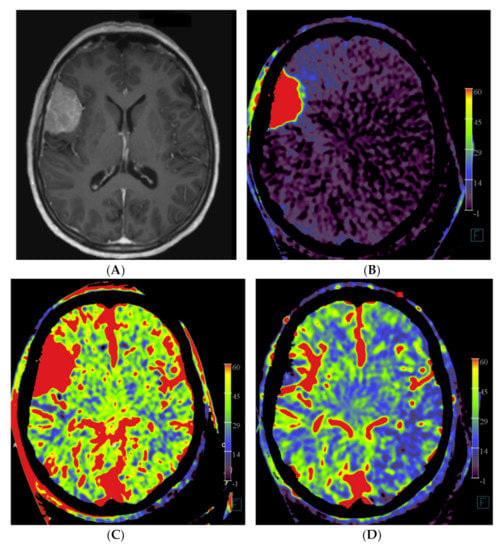

Figure 1.

Example of PBV images pre- and post-embolization with manually drawn regions of interest (ROIs) in a patient with a right frontal convexity atypical meningioma (patient no. 2). Axial post-contrast T1-weighted MRI image (A) shows the tumor with vivid enhancement and intralesional large vessels in a spoke wheel pattern. According to Wen et al. [21], handheld ROIs for PBV value measurements are drawn on PBV images after aortic root contrast injection in axial plane and in sagittal plane before embolization (axial reformation in (C) and sagittal reformation in (D) and after embolization (axial reformation in plane (F), reformation in sagittal plane is not shown) at the level of the largest tumor area. To confirm correct delineation of the PBV measurement area, PBV series were fused with the fill run series (B). Reference PBV measurement on the contralateral side was done using an elliptical ROI in sagittal plane reformation (E).